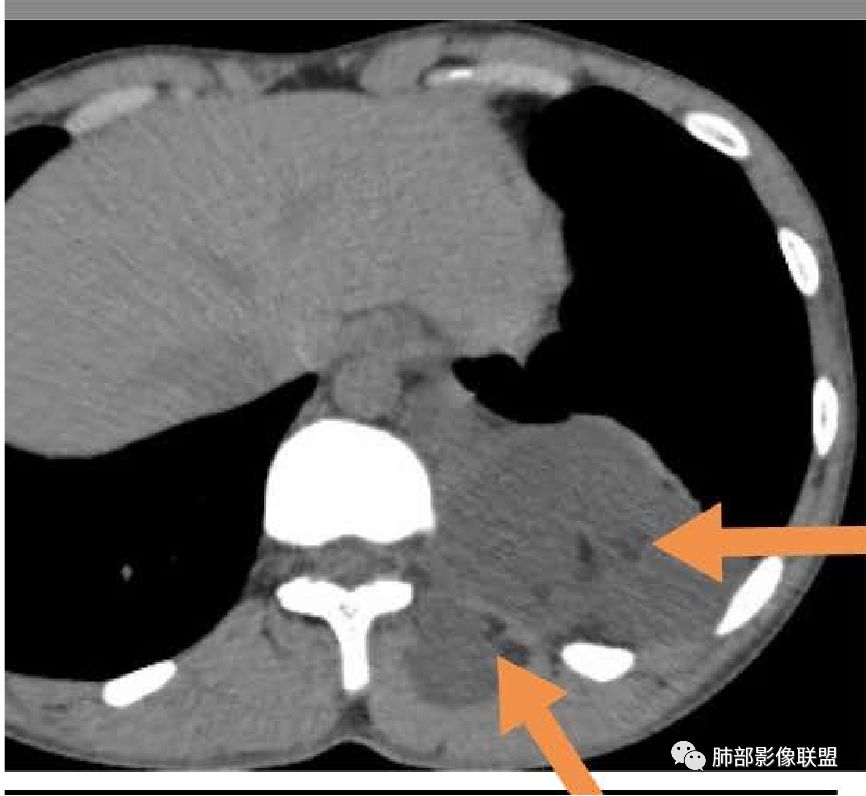

首先需要定位在哪?纵隔?胸壁?

应该是跨区域了。跨区域一般我们的分析:

1、病灶由一侧突入到另外一侧。

2、两个区域病灶融合,这一例好像符合后者。

常见的:管道相关的,血管、淋巴管,还有脂肪等。

这些脂肪是病灶本身的?还是病灶外的?

含脂肪?不含脂肪?对于性质的判断太重要了。

我觉得还是要考虑病灶内的可能性大一些。